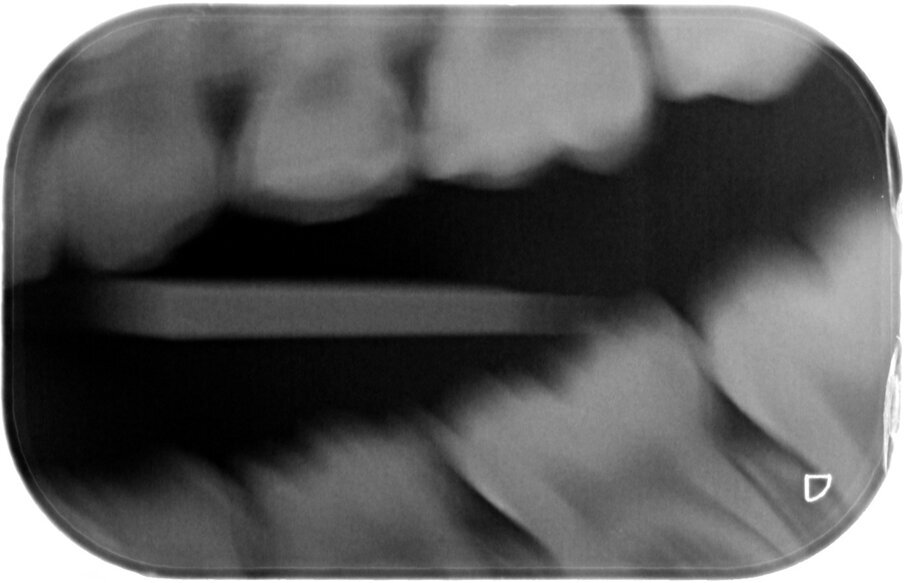

Groot voordeel van de Hall-techniek is dat deze eigenlijk altijd eenmalig is. De kans op herbehandeling vanwege loslaten, breuk, secundaire cariës of wat dan ook is lager dan bij elke andere therapie. De diepte of de grootte van de caviteit is van secundair belang. De prognose van de therapie wordt bepaald door de afwezigheid van pulpa-pathologie en door de aanwezigheid van een op een bitewing zichtbare laag van gezond dentine, ‘a clear band of dentine’, tussen de caviteit en de pulpa (afbeelding 12-13).

Afbeelding 12a-b. Casus 4: 21-02-18. BWR en BWL. Angstig meisje met pijn bij eten en poetsen bij 84 en 74.

Afbeelding 13a-b. Casus 4: 04-03-19. BWR en BWL na 1 jaar in 2 tempi middels de Hall-techniek succesvol zonder spuit, boor of angst behandeld.